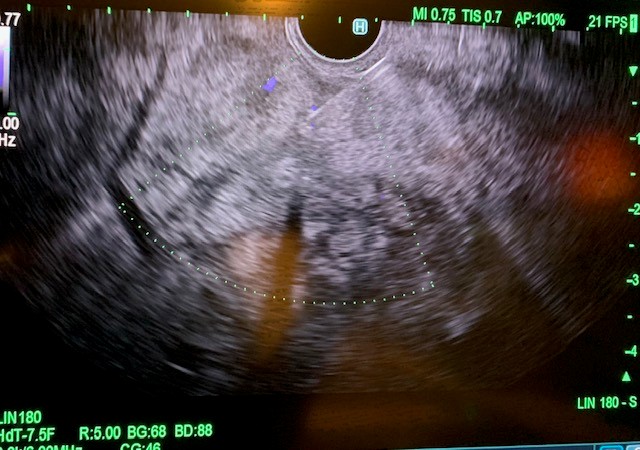

Under general anesthesia, esophagogastroduodenoscopy (EGD) was done using a gastroscope (Olympus America) and there were no esophageal or gastric varices noted. Next, EUS linear array echoendoscope (Olympus America) was passed into the esophagus and advanced into the stomach. The ultrasound image of the liver showed diffuse fatty infiltration. We performed portal pressure gradient using a 25-gauge Cook Echo Tip Insight needle (Cook Endoscopy, Winston Salem, NC). Pulse wave Doppler was used to confirm the middle hepatic vein. From the stomach through the left lobe of the liver, the middle hepatic vein was accessed, and three pressure measurements were taken using digital manometry (Figure 2). The average of 3 measurements from the middle hepatic vein was 17 mmHg. Pulse wave Doppler was used to confirm the left portal vein (Figure 3). Then from the stomach we measured the portal vein pressure by accessing the left portal vein and the average of three measurements was 18 mmHg (Figure 4), giving her a PPG of 1 mmHg. Using Doppler, we ensured there was no bleeding when the needle was withdrawn from both veins (Figure 5 and 6). After the portal pressure gradient measurement, liver core biopsies were done using a 19-gauge Boston Scientific FNB needle (Boston Scientific Marlborough, MA). From the stomach, the left liver lobe was biopsied with the use of EUS to confirm the absence of blood vessels in the needle’s trajectory. One pass and three actuations using the wet heparin technique was performed. The right liver lobe was biopsied from the duodenum and similar methodology was done using the same needle and technique. No bleeding was noted. Both core liver biopsies were sent in formalin to the pathology department for further evaluation.

Figure 1: Pulse wave Doppler of the middle hepatic vein.